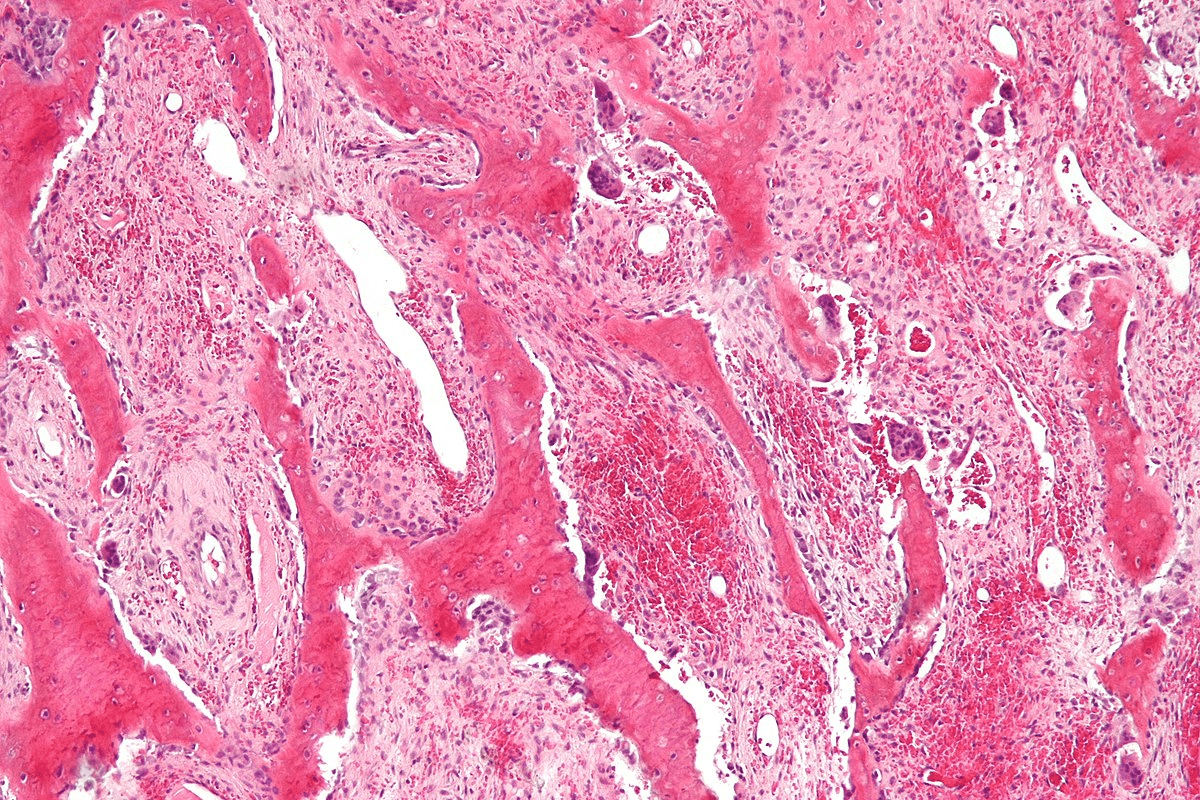

Osteolytic vs. Osteoblastic Lesions

Osteolytic lesions destroy bone, lowering bone density. Osteoblastic lesions, on the other hand, create abnormal bone, raising bone density.

- Osteolytic Lesions: These can lower bone density, increasing fracture risk.

- Osteoblastic Lesions: These can make bone density higher, but not necessarily stronger.